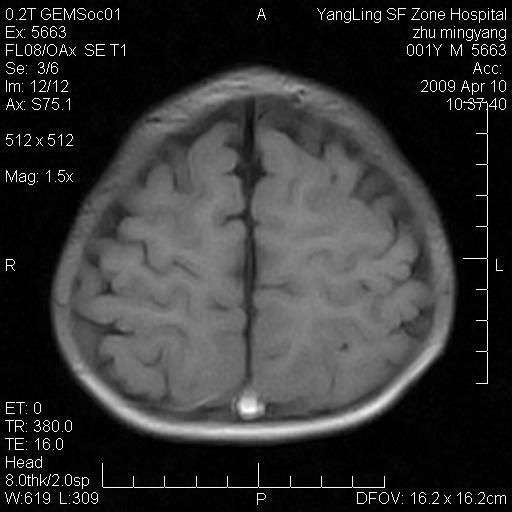

患者:1岁半,两天前外伤收住我院,ct检查小脑占位

考虑星形细胞瘤,建议增强

髓母细胞瘤或血管母细胞瘤,增强后可以鉴别;影像资料见 <。鱼博浪老师的《中枢神经系统ct与mr鉴别诊断》 小脑部肿瘤章节。

髓母细胞瘤或血管母细胞瘤!支持!

支持考虑髓母细胞瘤

考虑----髓母细胞瘤可能性大

考虑髓母细胞瘤或室管膜瘤。

支持髓母细胞瘤。

考虑髓母细胞瘤。

考虑髓母细胞瘤或星形细胞瘤

考虑髓母细胞瘤.

考虑髓母细胞瘤可能性大。

小脑肿瘤.考虑髓母细胞瘤可能.

就病灶部位及临床资料首先考虑髓母.